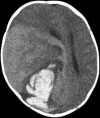

Novel PPP1CB-ALK fusion protein in a high-grade glioma of infancy